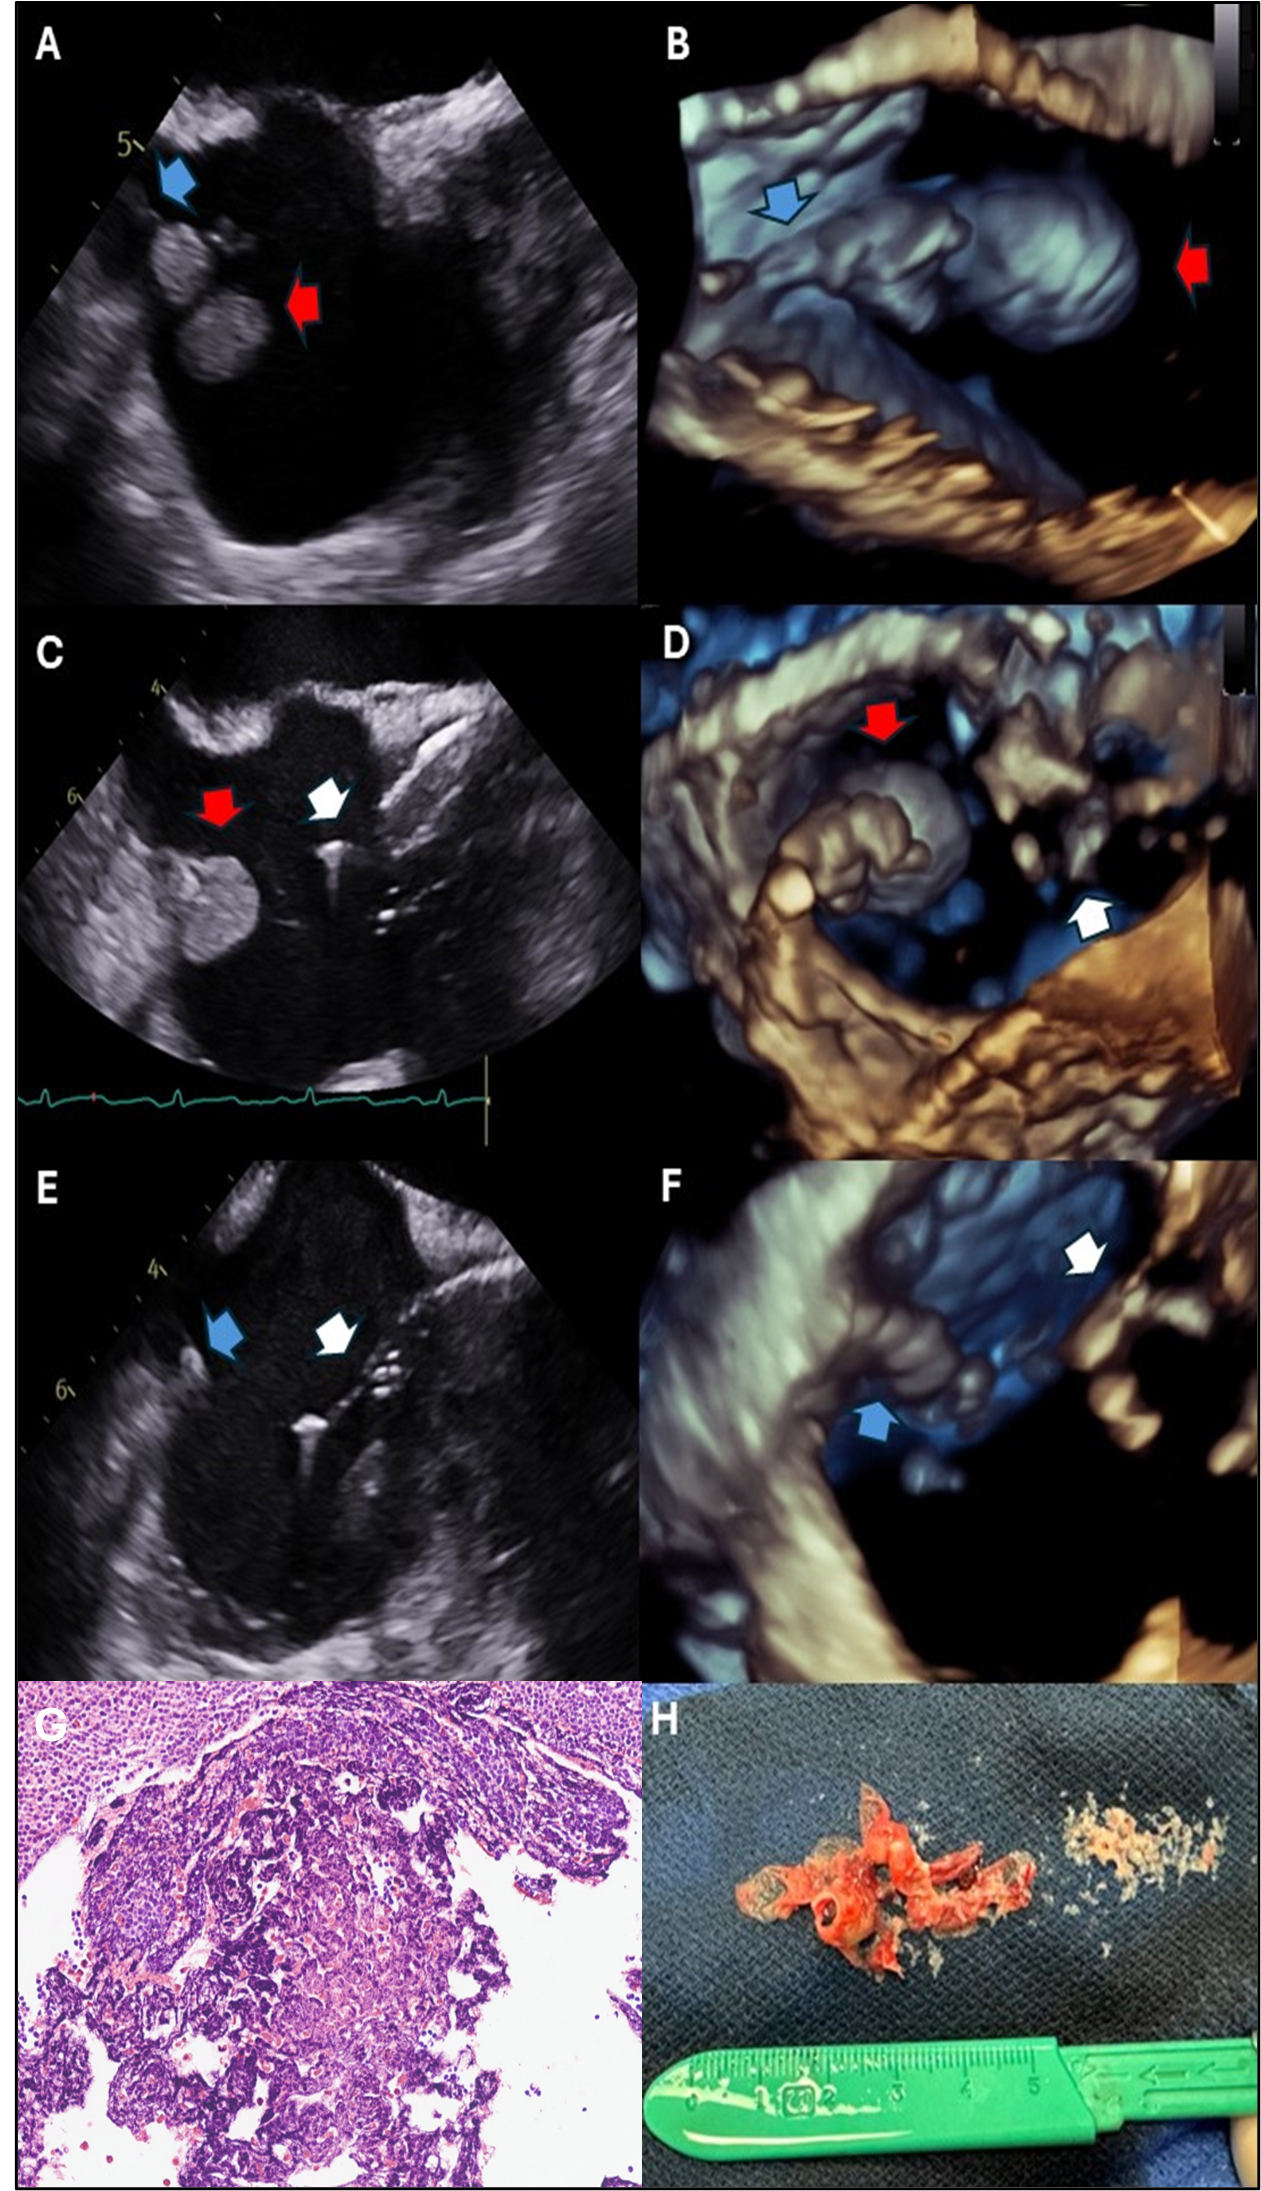

A 59-year-old man with heart failure with reduced ejection fraction (HFrEF) and a single-chamber implantable cardioverter-defibrillator presented with group B streptococcus bacteremia. Transesophageal echocardiography (TEE) revealed a 2.4 x 1.5-cm vegetation on the atrial portion of the right ventricular lead (Figure A and B). Due to the embolization risk with extraction alone, percutaneous mechanical aspiration (PMA) using the AngioVac system (AngioDynamics) was pursued. The AngioVac system, consisting of aspiration cannulas connected to a veno-venous perfusion circuit, was inserted via the right internal jugular vein. Under TEE guidance, the aspiration catheter removed the vegetation (Figure C-F) and then repositioned to capture residual vegetative material. The lead was successfully extracted and pathology confirmed infection (Figure G and H). For CIED vegetations, percutaneous mechanical aspiration followed by extraction may reduce embolization risk.